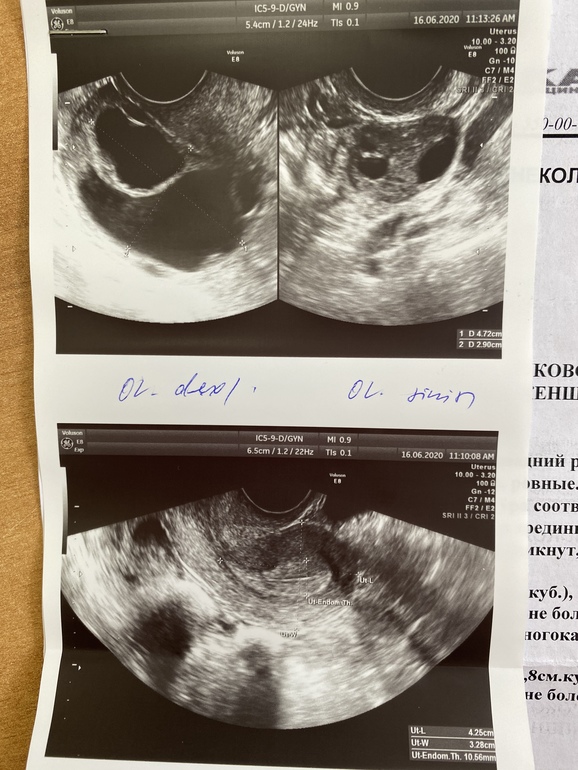

И вот сейчас 27дц. Пыталась тестами ловить О, но без результатов. Решила что её не было( у меня она вообще редкое явление). Так вот на 21дц решила сходить на узи, посмотреть что да как там. Обнаружили кистозное образование в правом яичнике. Но так как я по узи не следила, то узили не смогла сказать овуляция это была или это вообще с прошлого цикла осталось. А мне на 4-6дц ехать к Ре, крио по программе. Так вот скинула своей РЕ результаты. Говорит могла быть О и к двум таблеткам дюфастона (я пью его всегда с 16-25дц) сказала добавить ещё одну и на 28-29дц сдать кровь на хгч. Тесты не делала, я особо надежд не питаю, но так страшно опять разочаровываться. Сил с каждым разом все меньше. За плечами 9 лет попыток. Сильно колит периодически справа, все таки я склоняюсь, что это просто киста(( Прилагаю фото узи. Может у кого было подобное и в итоге вышло чудом?))